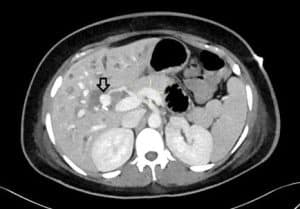

Subsequently, she underwent computed tomography (CT) abdomen and pelvis with contrast, which showed a lobulated saccular dilatation of the right hepatic artery, suggesting pseudoaneurysm formation (Figure 1). It was found in close proximity to surgical clips within the gallbladder fossa. There was also associated moderate intrahepatic ductal dilatation with ducts containing hyperdense material, like blood products.

Figure 1: CT abdomen axial maximum intensity projection images